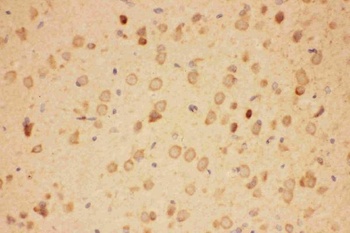

10 μg, 100 μg - Anti-HSPB8/Hsp22 Antibody [orb18992]

FC, ICC, IF, IHC, IP, WB

Human, Mouse, Rat

Rabbit

Polyclonal

Unconjugated

100 μg, 10 μg - Anti-CPI17 alpha/PPP1R14A Antibody [orb19175]